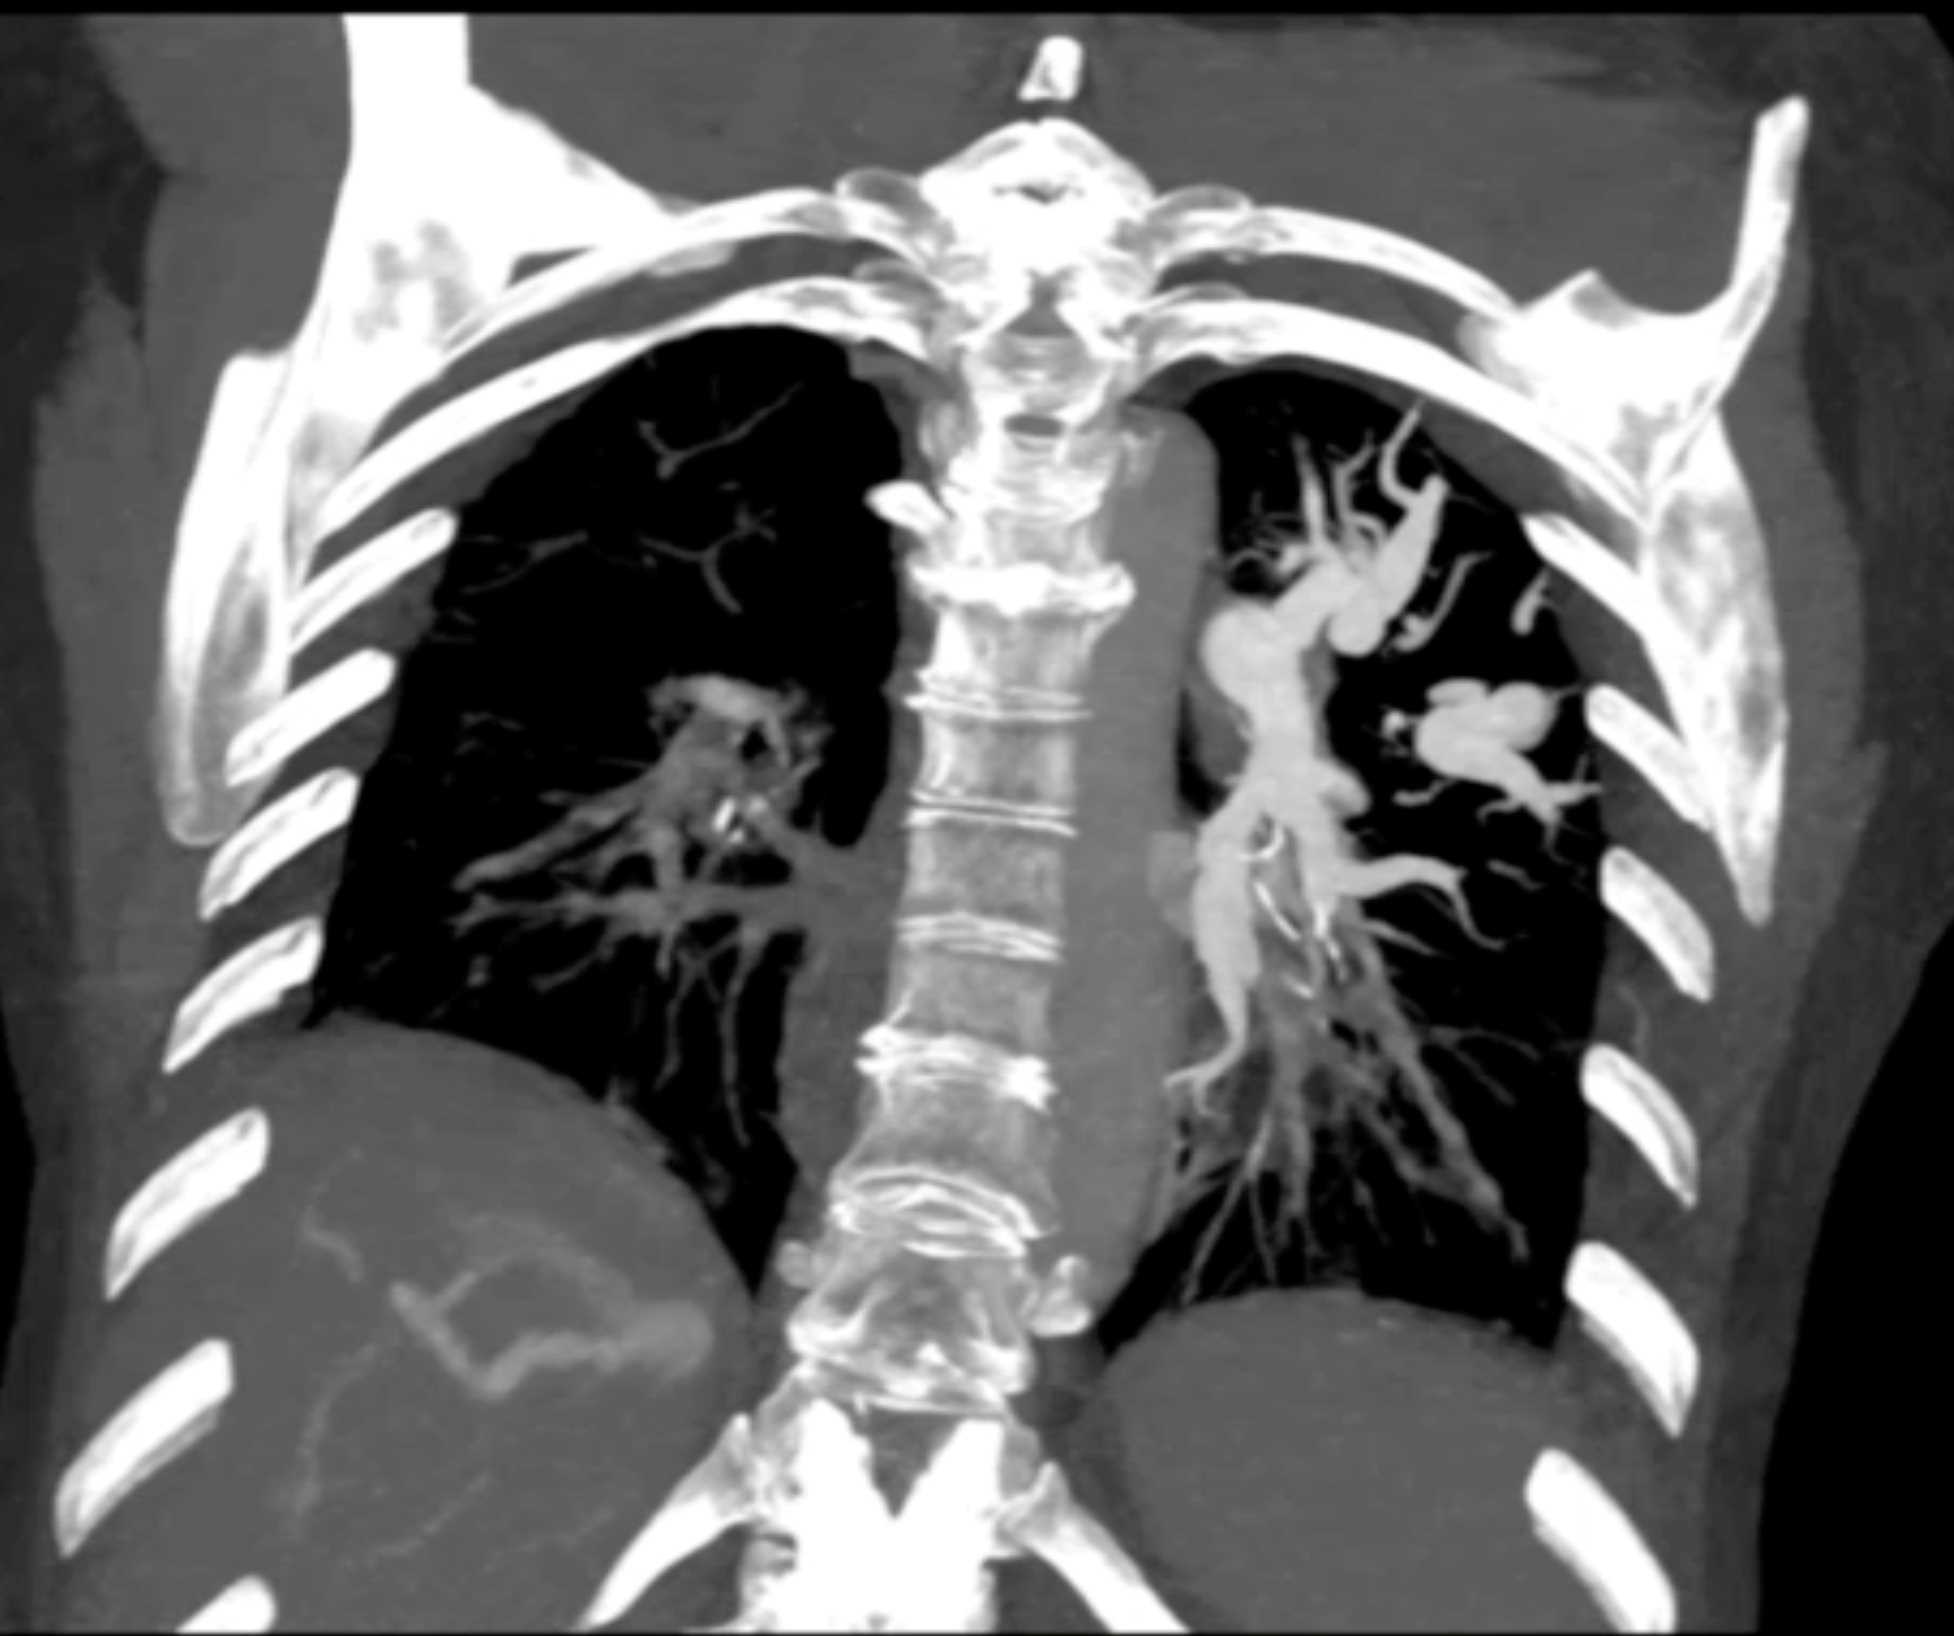

Fibrosing Mediastinitis involves the Pulmonary Artery and Vein